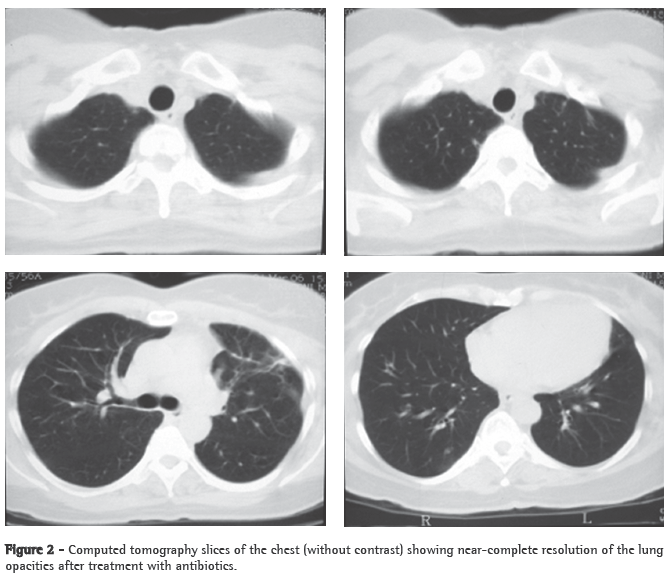

A 56-year-old Caucasian female sought treatment in the emergency room presenting a painful, right-sided neck tumor for 5 days. The patient reported a dry cough and high fever for 3 days. She described herself as a nonsmoker. She was hypertensive and diabetic. She had experienced a myocardial infarction 3 years prior. At admission, the patient was dehydrated and afebrile (axillary temperature, 36.7°C). She presented normal respiration. Laboratory tests revealed increased erythrocyte sedimentation rate (92 mm). Ultrasound of the neck showed IJV thrombosis, and anticoagulation was started on post-admission day 4. A chest X-ray demonstrated at least two nodules in the left lung, one apparently cavitated and one with a diameter of 18 mm at its base, as well as an irregular lesion, 25 mm in diameter, in the right upper lung lobe. A transesophageal echocardiogram, performed in order to rule out endocarditis, demonstrated no vegetation. Due to the hypothesis of pneumonia, empirical treatment with oral cefuroxime (500 mg every 12 h) was started. A computed tomography scan of the chest revealed multiple bilateral lung opacities, with an aspect suggestive of metastatic implants (Figure 1). The patient was then submitted to fiberoptic bronchoscopy, the findings of which were normal. In the microbiological analysis of the bronchoalveolar lavage fluid, testing for acid-fast bacilli and fungi were negative, as were the cytopathologic study and cultures. Since the working diagnosis was metastatic neoplasm, the patient underwent surgical lung biopsy. The anatomopathological examination of the sample showed chronic suppurative inflammation with organizing abscesses in lung parenchyma. In view of the hypothesis of Lemierre's syndrome caused by jugular thrombosis accompanied by septic pulmonary embolism, the patient was questioned regarding the occurrence of tonsillitis at the onset of the disease. The patient had no recollection, but her daughter remembered that the patient had used oral amoxicillin (500 mg every 8 h for 10 days) for the treatment of tonsillitis some days prior to hospitalization. At hospital admission, the patient received a course of intravenous cefuroxime (750 mg every 8 h for 7 days) concomitantly with oral azithromycin (500 mg once a day for 5 days). Subsequently, because fever persisted, she was treated with cefepime (1,000 mg every 12 h for 7 days). A control computed tomography scan of the chest performed after this course of antibiotics showed nearly complete resolution of the opacities (Figure 2). The patient had been afebrile since the third day of the new course of antibiotics. No microorganisms were isolated from blood cultures or bronchoalveolar lavage cultures. Since there is no evidence that it is beneficial in cases of Lemierre's syndrome, anticoagulation was discontinued after 20 days.

Pulmonary involvement in this syndrome is extremely common (seen in up to 97% of the cases). Pulmonary lesions can manifest on the first day of sepsis. There can be intense pleuritic pain with dyspnea, and hemoptysis often occurs. Pulmonary auscultation can reveal localized crackling rales and pleural friction rub. Chest X-rays typically show multiple bilateral opacities and small pleural effusions. It is possible to detect cavitation on the first X-ray. There can be rapid progression of the lesions, even with the use of antibiotics. Empyema develops in 10% to 15% of cases. Abscess, pneumothorax and pneumatoceles have been described. After contrast administration, there is peripheral enhancement of the lesions with central areas of decreased attenuation. The differential diagnosis should be made with pneumonia (acute bacterial, atypical, aspiration and staphylococcal pneumonia).(1,2,11-14)